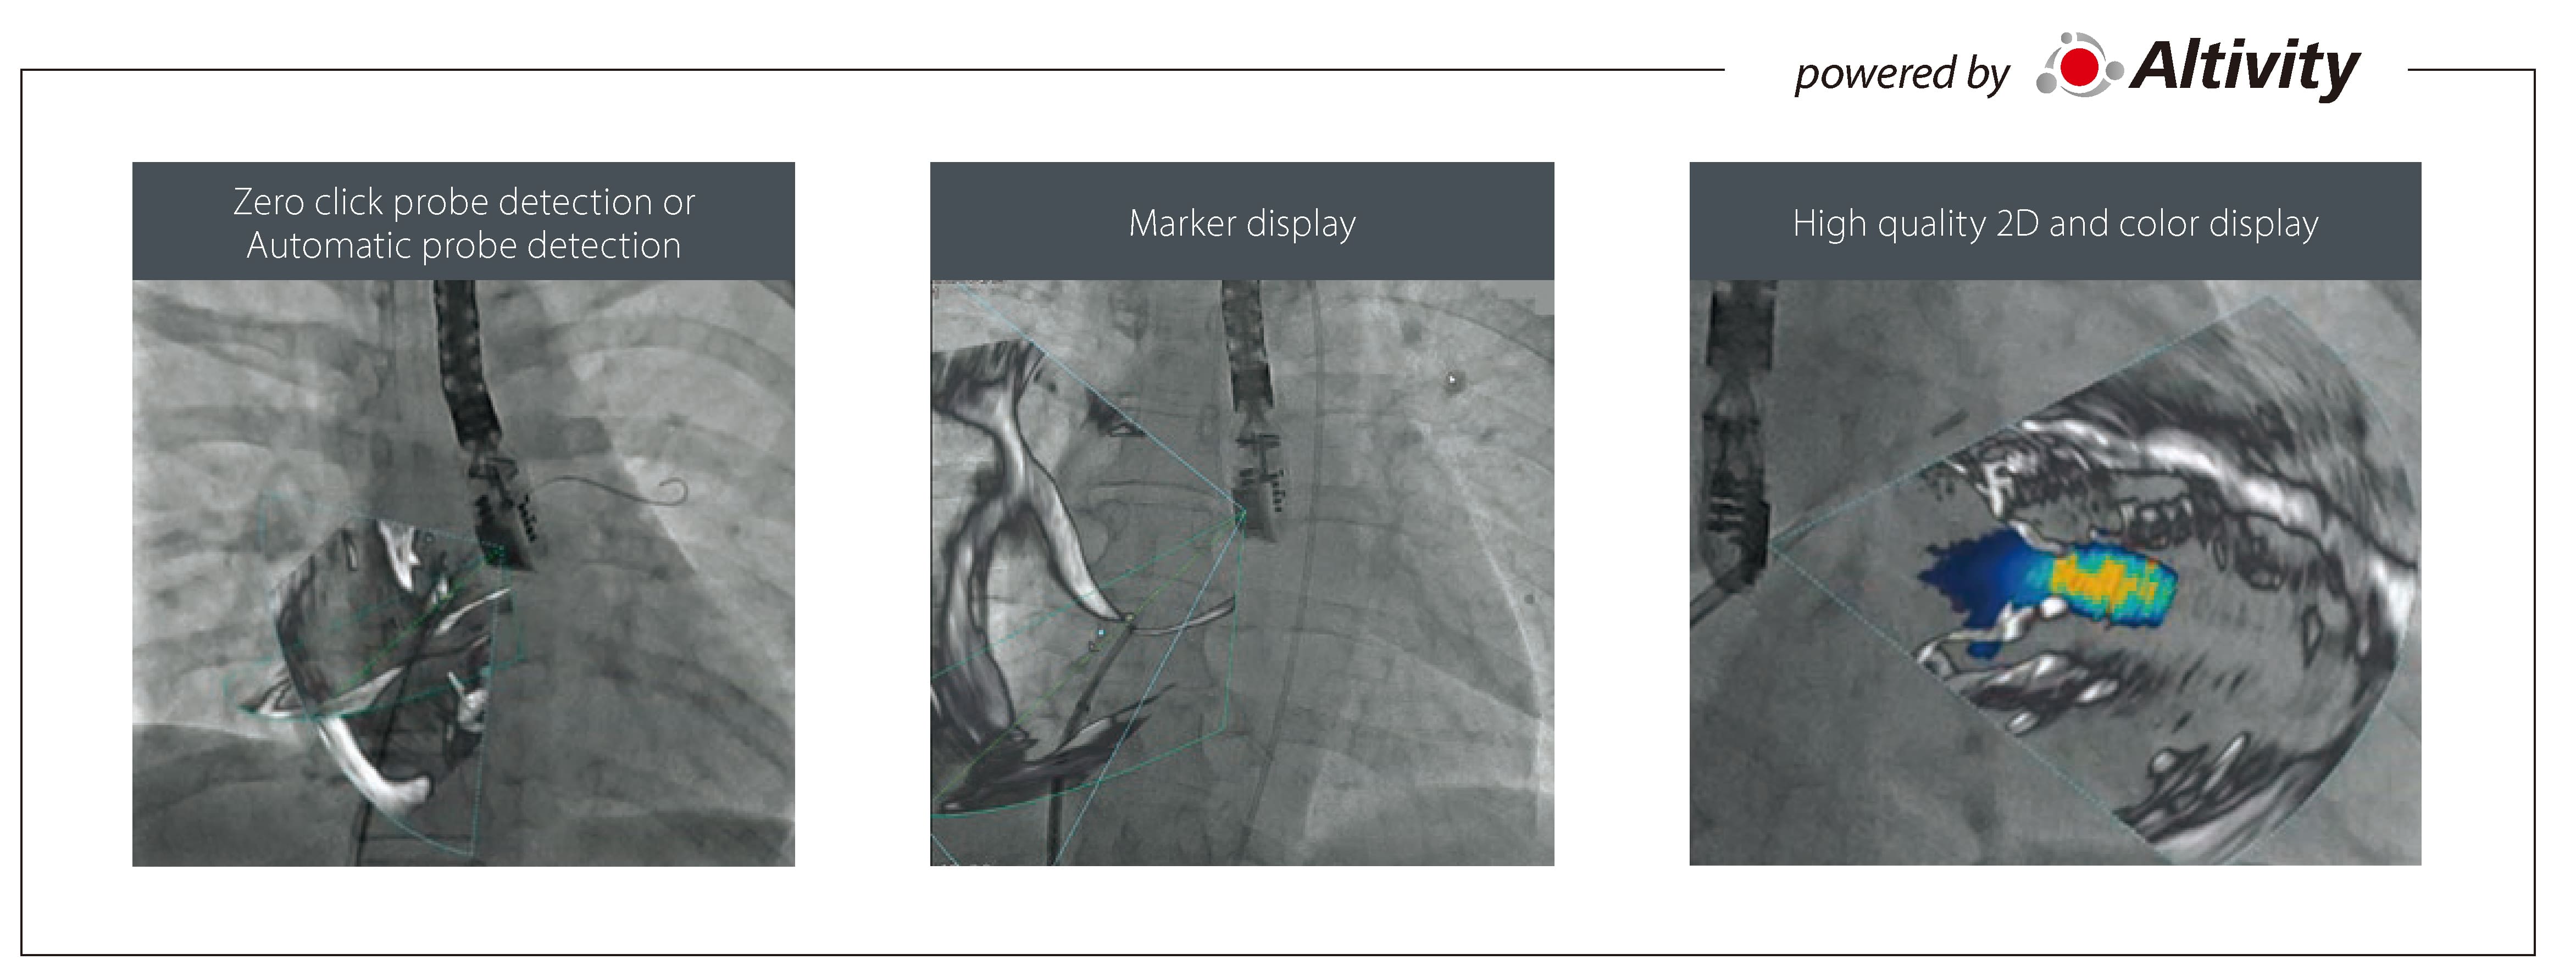

-Accurate Stenting with Dynamic Device Stabilizer (DDS)

Interventional Cardiologists face challenges with stent visualization, device positioning and expansion. DDS utilizes deep learning to automatically detect balloon markers in real-time, magnifying and stabilizing the image on a separate screen to assist visualization and assessment.

-Support Structural Heart Disease (SHD) treatment with Echo Fusion

Complexity in Structural Heart Disease is increasing, with new procedures requiring accuracy and efficiency. With intelligent Deep Learning technology, Echo Fusion automatically identifies the echocardiography probe and fuses the fluoroscopic image without additional operator input.

-Echo Fusion facilitates the communication between the interventional X-ray system and the ultrasound machine that are used in tandem for Structural Heart Disease (SHD) procedures.